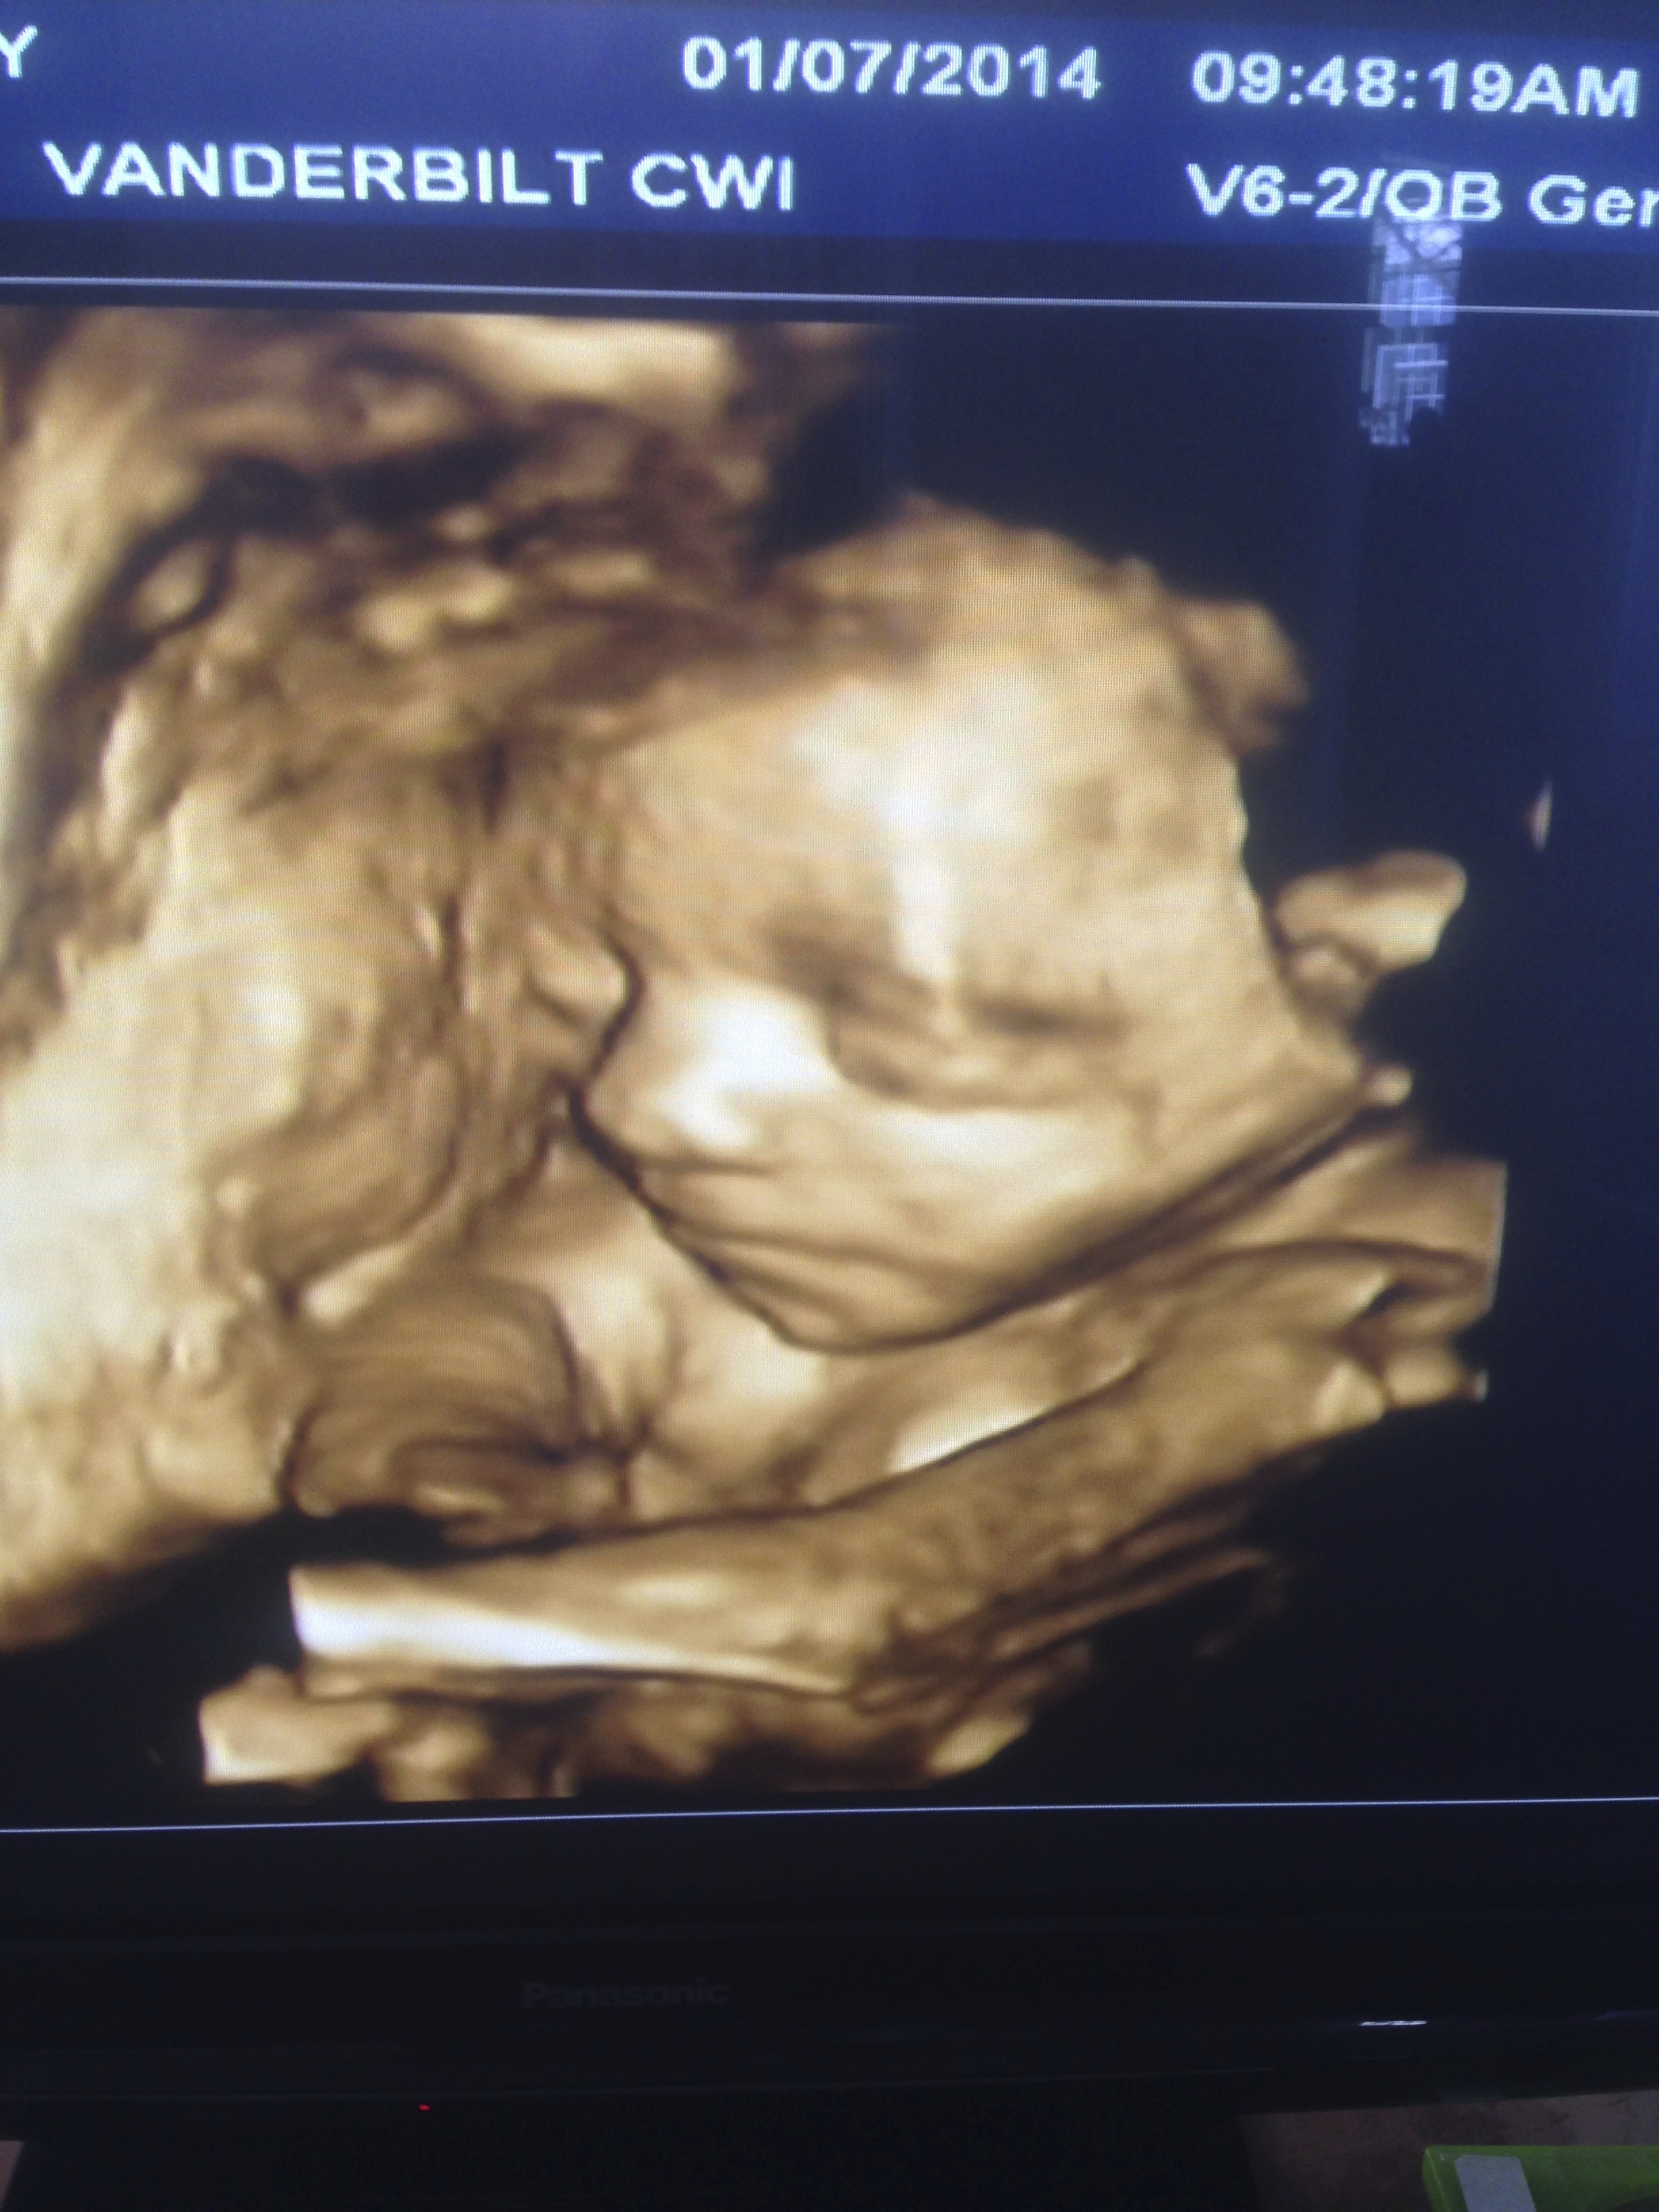

Yesterday we took a bus downtown and weaved through the streets of Mérida, watching our step along the way. The boy was intent on finding a black rope to buy, which became a public situation until we found some balloons. I love and hate these types of solutions. It was kinda weird how we could find every other color of rope, but no, not a black one. We waited an hour-ish for the bus home. Meanwhile there we are standing streetside in this old, marching city and I start to feel green. I mean green and dizzy, I guess. Sitting down wasn’t a good option, so I just tried to focus on specific cracks in the wall. All we needed was one R1 bus to come at us, none of this R2, R3 mess. And I’m sweating at least 25% more than normal, I’d say. If I had been alone, just me and little one inside, I would’ve cashed out and found a coffee shop or a glass of wine somewhere. So obviously traveling with a smaller one changes things up a bit, mainly affecting the crevices and every detail of a trip. This kid’s incredible though, powerful as he tells me on occasion, so we’ll be making our way through our days together here and I’m good with it.